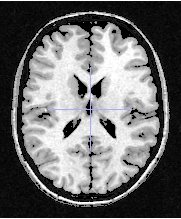

Test image, tex_min = 0, tex_max = 4095

Mode Description Mode_no_binary : fasle Mode_binary : true

great_than to select all the voxels for which value of levels of gray is larger than the threshold1

Threshold1 = 350